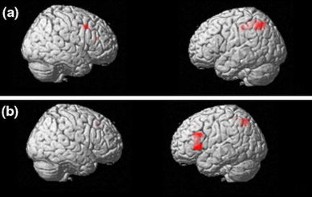

Emotional processing may be abnormal in amyotrophic lateral sclerosis (ALS). Our aim was to explore functional anatomical correlates in the processing of aversive information in ALS patients. We examined the performance of nine non-demented ALS patients and 10 healthy controls on two functional MRI (fMRI) tasks, consisting of an emotional attribution task and a memory recognition task of unpleasant versus neutral stimuli. During the emotional decision task, subjects were asked to select one of three unpleasant or neutral words. During the memory task, subjects were asked to recognize words presented during the previous task. Controls showed, as expected, greater activation in the right middle frontal gyrus during selection of unpleasant than neutral words, and a greater activation mainly in right-sided cerebral areas during the emotional recognition task. Conversely, patients showed a general increase in activation of the left hemisphere, and reduced activation in right hemisphere in both emotional tasks. Such findings may suggest extra-motor neurodegeneration involving key circuits of emotions, mostly negative, commonly involved in FTD.